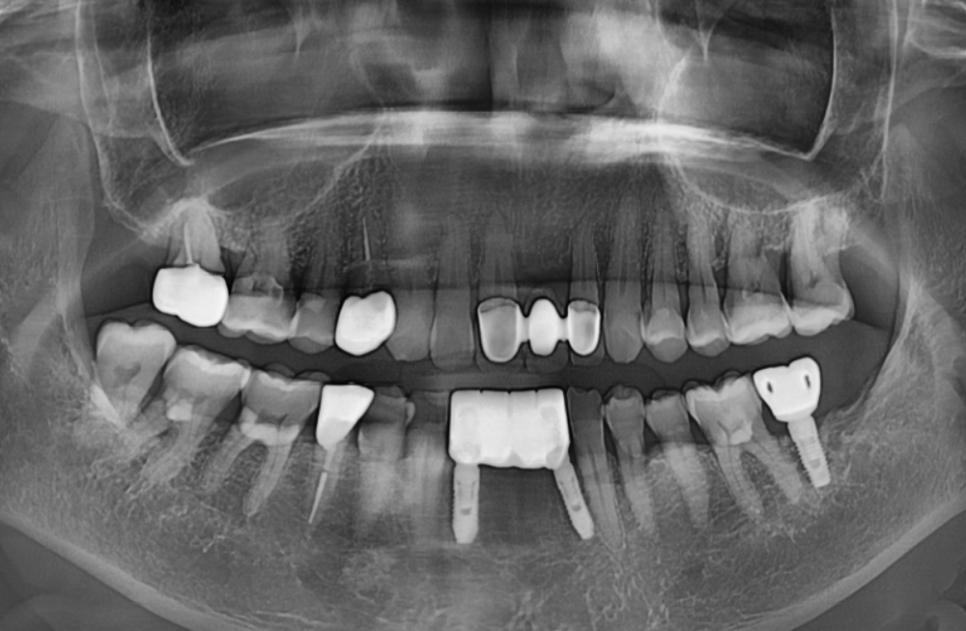

이번 환자분도 구강 스캐너로 본을 떴는데,

정밀하게 스캔이 잘 돼서

보철이 당일에 바로 잘 맞았습니다.

230901

보통 임플란트 보철을 장착할 때는

높이, 맞물림, 간섭 등을 확인하면서

조금씩 조정하는 과정이 필요한데,

이번 케이스는 크게 조정할 게 거의 없었어요.

색상도 자연스럽고,

모양도 만족스러운 결과가 나왔습니다.^^